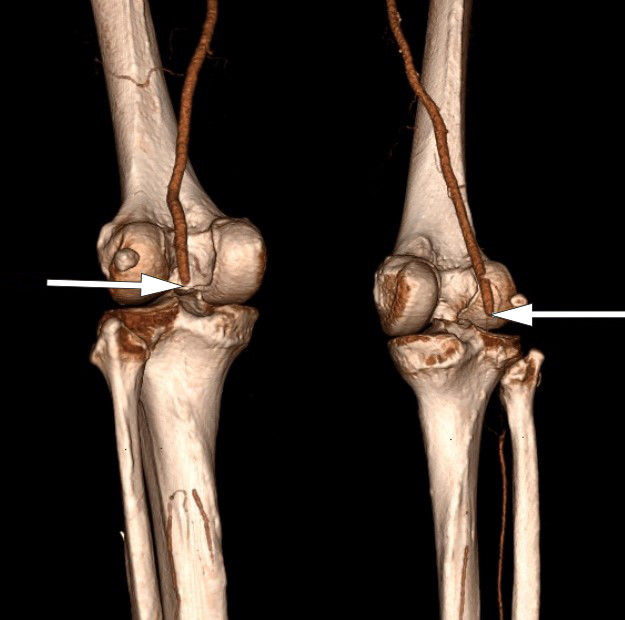

A PCR test on admission was negative for COVID-19 and the patient had no respiratory symptoms. CT angiography showed a filling defect from both popliteal arteries in the knee joint (Figure 1). He also had occlusions distally with localised refilling in the calf arteries, consistent with thrombosis in both lower extremities. The patient was given 5 000 IU dalteparin before being transferred to a regional hospital.